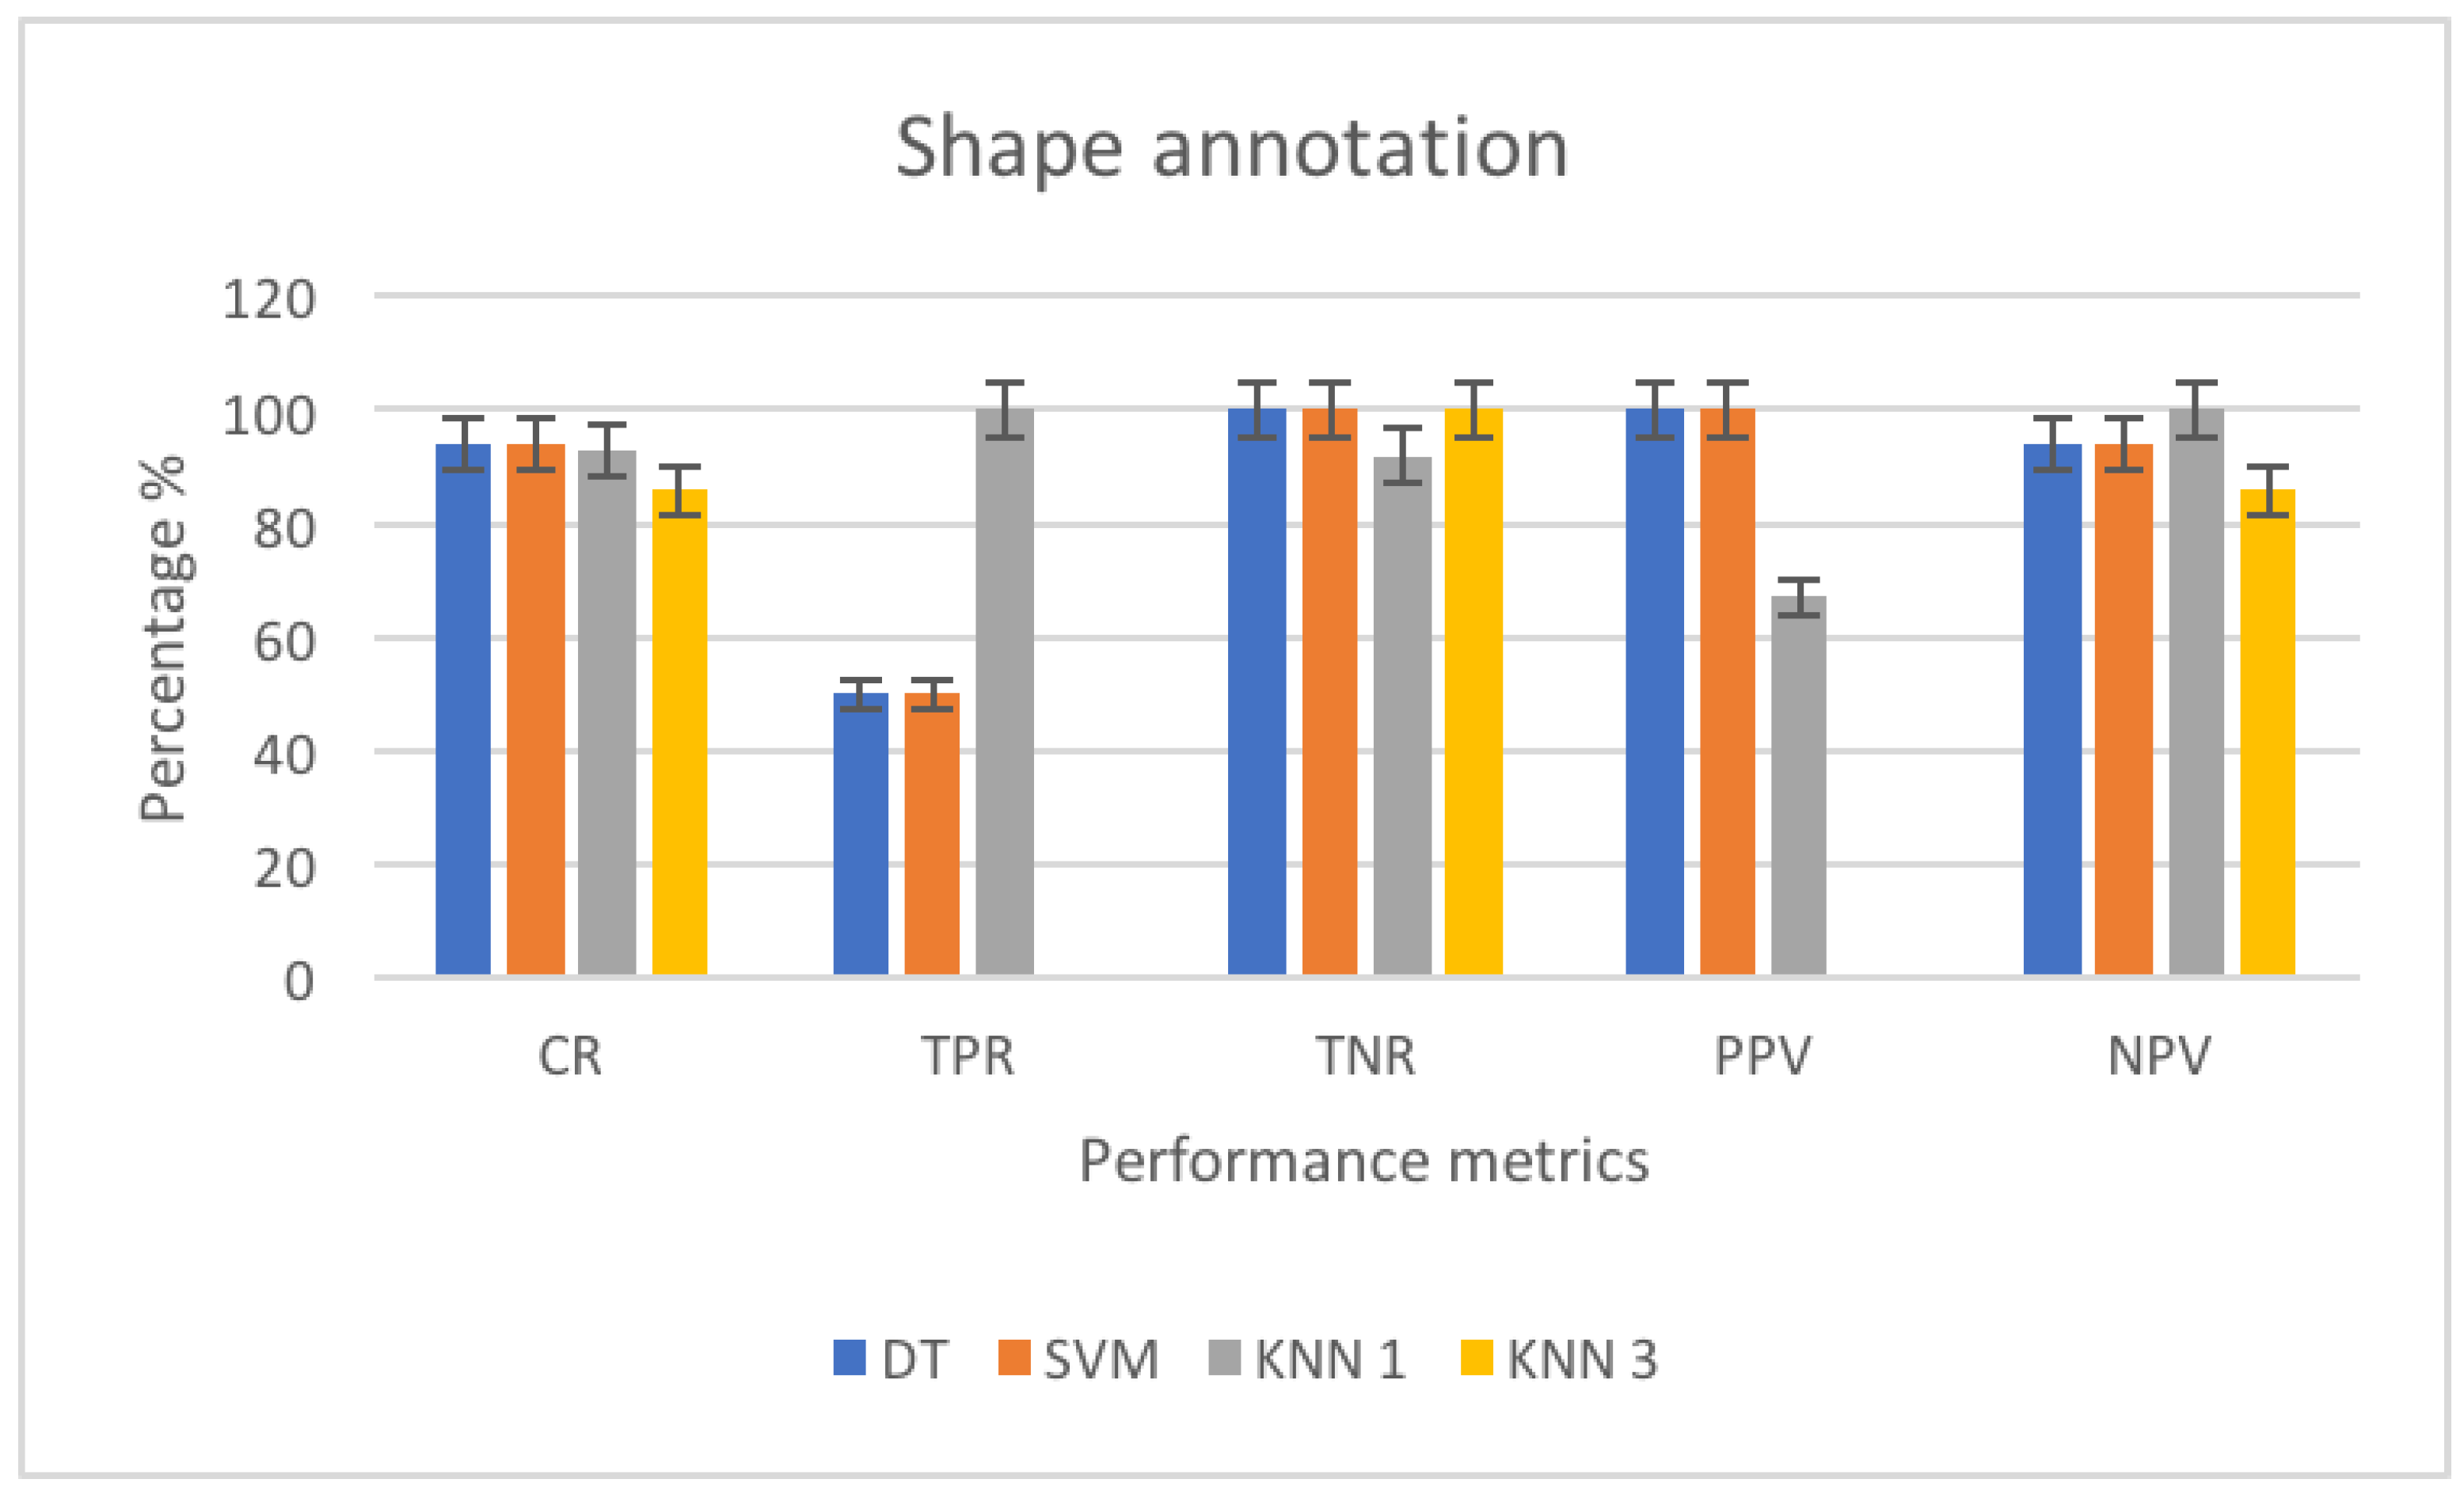

3.4.3. Shape Annotation